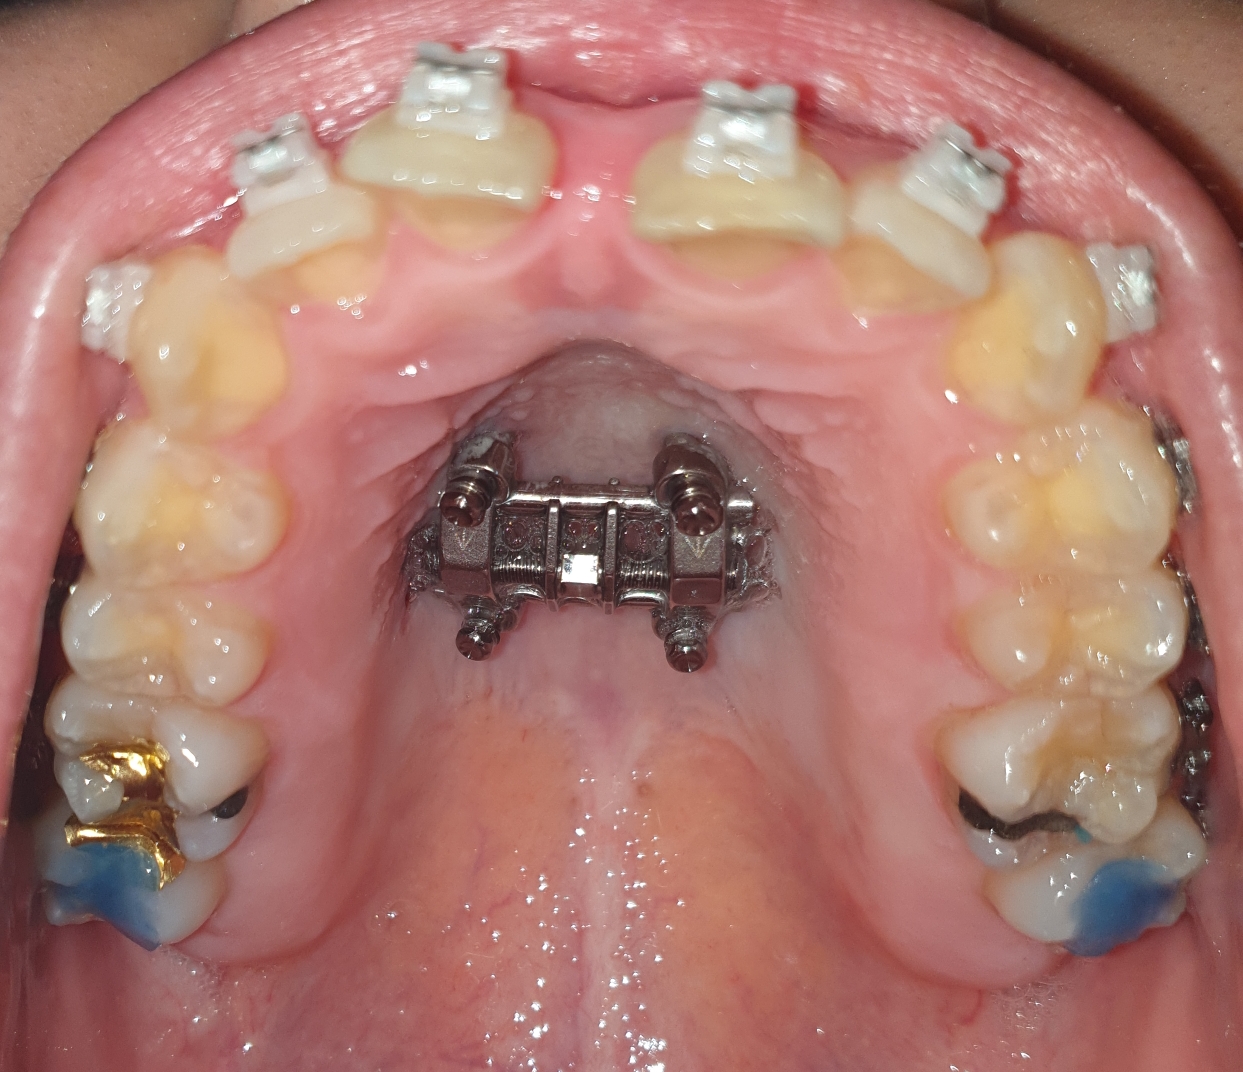

교정일기-상악악궁 확장기 다리, 반지 제거, 상악 브라켓 붙이기

안녕하세요. 지난 일주일간 앞니가 많이 벌어졌어요. 한 5mm이상은 벌어진 것 같네요. 앞니는 계속 아프다가 수요일 쯤 괜찮아졌어요. 바이트 블럭과 아픈 앞니로 인해 슬프지만 음식은 가위 들고 다니면서 야무지게 잘라 먹었답니다.

7월 25일에 병원에 갔더니 더 이상 확장하지 않는다고 했어요. 그래서 다리랑 반지를 제거했어요.

제거할때 톱같은거로 제거하는거 아닌가, 상처가 나지 않을까 걱정했는데 크게 아프지는 않았어요. 어떤 도구로 하는지는 모르겠지만 한번에 지이잉 툭! 이런 느낌이 아니라 지이잉 지이잉 여러번 대면서 갈더라구요. 따끔따끔 할 거예요 라고 하셔서 아, 따끔거리는 건 당연한거구나. 상처가 나지는 않는가 보네 했는데 왠걸, 입천장 계속 따끔거리고 소독솜 물고 지혈을 시키는 것 같더라구요. 다리가 너무 살과 가까워서 어쩔 수 없었대요.

그러고 나서 상악 브라켓을 붙였어요. 와이어는 끼우지 않고 한 달 후에 오면 된다고 했어요.